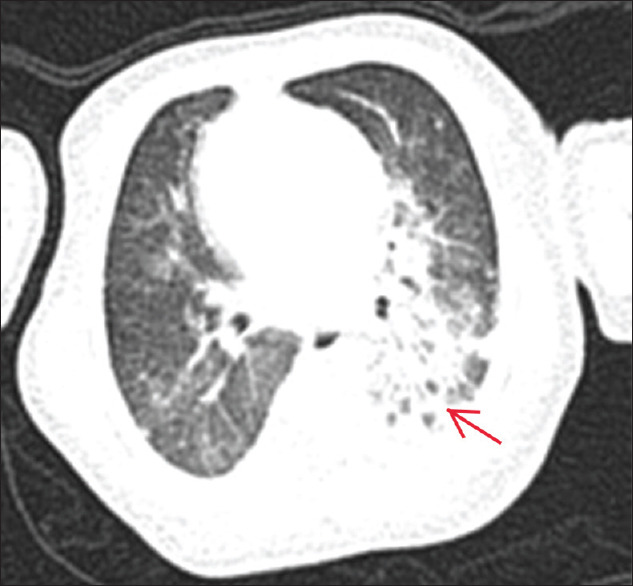

Congenital pulmonary airway malformation (CPAM) together with oesophageal atresia and tracheoesophageal fistula (TOF) is a very rare condition in neonates. We presented a case of an infant with Gross type C oesophageal atresia with TOF coexisting with Stocker Type III CPAM in our centre. It is interesting to know that TOF associated with type III CPAM has never been reported in the literature. The child was delivered through caesarean section, and because of respiratory distress post-delivery, endotracheal intubation was carried out immediately. CPAM was diagnosed by a suspicious finding from the initial chest X-ray and the diagnosis was confirmed through computed tomography scan of the chest. The patient was initially stabilised in a neonatal intensive care unit (NICU), and after the successful ligation of fistula and surgical repair of TOF, lung recruitment was started by high flow oscillatory ventilation. The patient recovered well without complications and able to maintain good saturation without oxygen support through the stay in the neonatal unit. Early recognition of this rare association is essential for immediate transfer to NICU, the intervention of any early life-threatening complications, and for vigilant monitoring in the postoperative period.